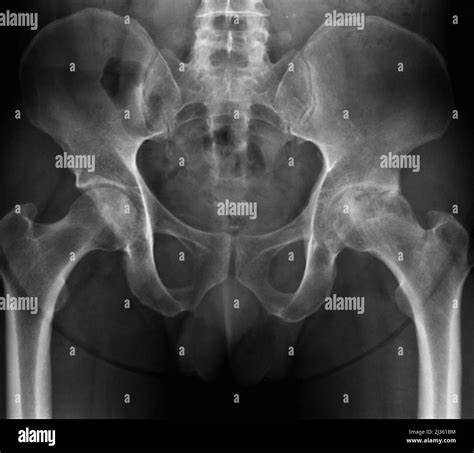

Now, let’s get into which joints are most often affected by osteoarthritis and what specific symptoms you might experience in those areas. Knee osteoarthritis is super common. You might feel pain when walking, climbing stairs, or even just standing for a long time. Stiffness and swelling are also frequent culprits. It can make everyday activities like getting in and out of a car or playing with your kids feel difficult. Next up, we’ve got hip osteoarthritis . This can cause pain in your groin, thigh, or even your buttock. The pain often gets worse with activity and can limit your ability to walk or stand for extended periods. Sometimes, you might feel a stiffness that makes it hard to put on socks or shoes. Hand osteoarthritis often affects the finger joints. You might notice bony bumps or nodules on your fingers, along with pain and stiffness. This can impact your ability to grip things, open jars, or even type. The base of your thumb is also a common spot for OA in the hands. Spine osteoarthritis is another area that can be hit. This can lead to lower back pain and stiffness. You may also experience pain or numbness radiating down your legs. This is sometimes called spinal stenosis. It can make bending, twisting, or lifting a real struggle. Lastly, foot and ankle osteoarthritis is also possible. This can cause pain when walking or standing, along with stiffness and swelling. It can make it difficult to find comfortable shoes and limit your mobility. Remember, it’s not always easy to pinpoint the exact cause of your joint pain, so consult a doctor to get an accurate diagnosis.